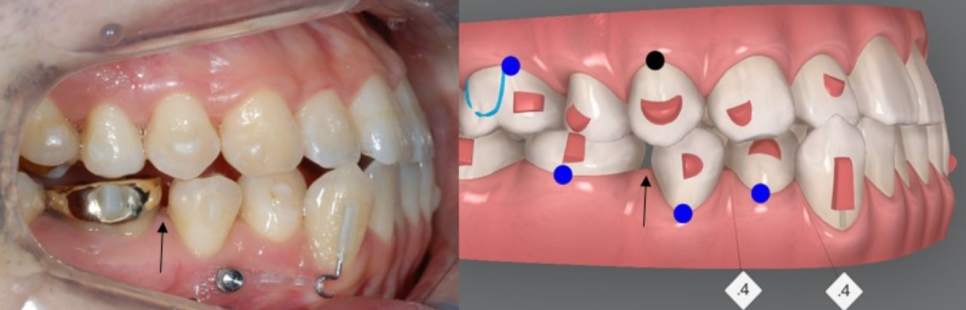

교정을 시작하기 앞서

같은 원장님께 교정, 충치치료까지 가능한

유펜바른치과에서

충치치료를 마무리 해드리고 교정을 진행해드렸습니다 :)

2nd(31개)

두번째 클린체크에서도

우측 아래 치아 전체를

뒤로 미는것에 중점을 두어

큰 어금니들을 먼저 뒤로 밀며 생기는 사이의 틈을 이용해

앞니들을 가지런하게 배열해주었습니다.

어금니들의 대 이동!

쉽지 않은 과정이었지만 닥터킴은 섬세한 치료의 마무리를 위해

다음 클린체크를 이어나가셨습니다 :)